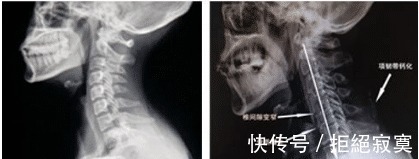

主要由于颈椎长期劳损、骨质增生,或椎间盘脱出、韧带增厚,致使颈椎脊髓、神经根或椎动脉受压,出现一系列功能障碍的临床综合征。表现为椎节失稳、松动;髓核突出或脱出;骨刺形成;韧带肥厚和继发的椎管狭窄等,刺激或压迫了邻近的神经根、脊髓、椎动脉及颈部交感神经等组织,引起一系列症状和体征。